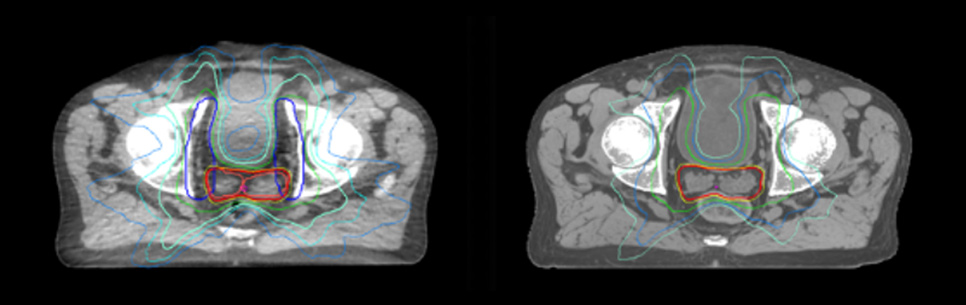

Evaluation of MRCAT dosimetric accuracy

Dosimetric equivalence validation was performed on 43 patient cases by comparing MRCAT-based dose plans overlaid on CBCT image dataset and on the corresponding MRCAT image dataset. Mr. Bolard and Dr. Champion found good agreement between MRCAT-based and CT-based dose calculations, with a mean dose ratio of 1.007 (0.991-1.014). The 3D gamma score was greater than 95% (95.2-99.0%) for all plans checked. A poster on this work was accepted for presentation at ESTRO 2020.

Dose plans overlaid on CBCT image dataset (left) and on MRCAT image dataset (right).

Prostate MR-only radiotherapy planning with use of rectal spacer

Hôpital de La Tour uses an implanted rectal spacer (SpaceOAR®, Boston Scientific) for patients receiving prostate radiotherapy to provide space between the rectum and prostate. 3D T2W TSE MRI provides excellent rectal spacer visualization and is used for OAR and target contouring. The dose plan is calculated on the MRCAT dataset.

Simulation imaging

Tranversal 3D T2W TSE with Compressed SENSE, acquired on Ingenia MR-RT 1.5T (left).

On-console generated MRCAT (right).

MR-based contouring and planning

MRCAT is primary image dataset for dose calculation (left).

3D T2W TSE MRI with 36 cm Field-of-View is used for delineation of prostate and organs at risk (right).